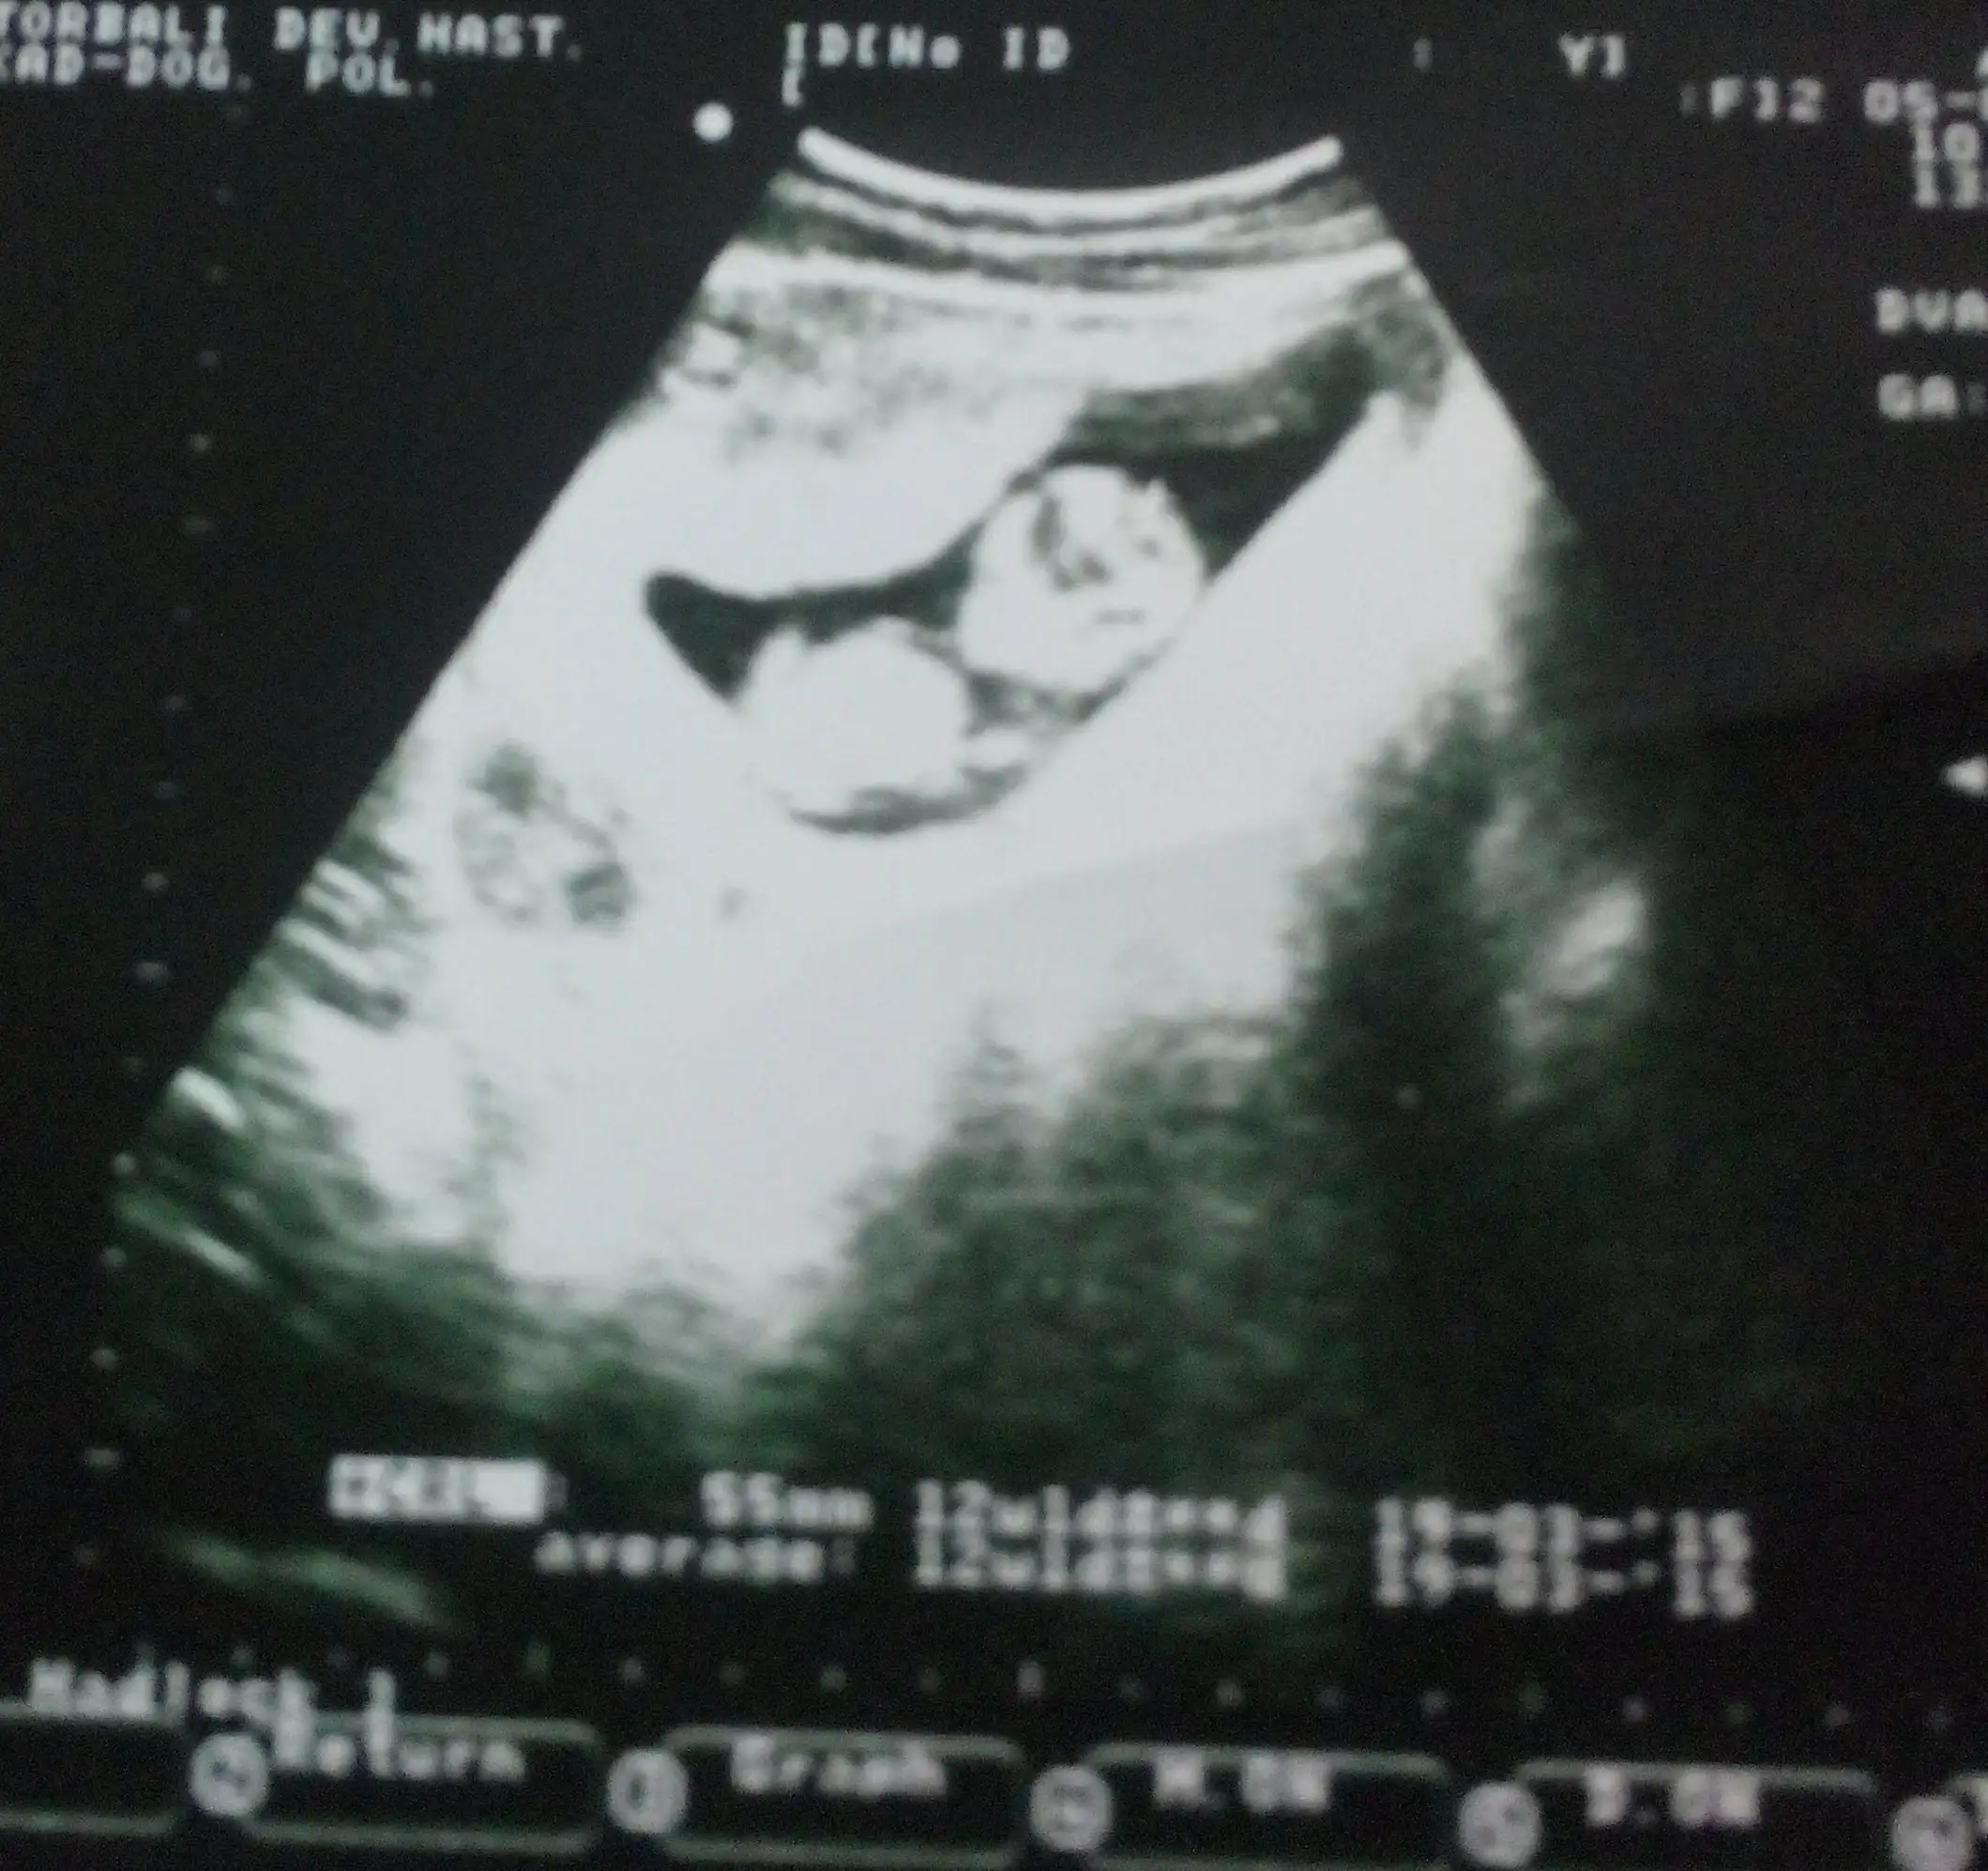

Merhaba arkadaşlar benim bebegim daha çok minnak :) ultrason görüntüsüne göre 9 haftalık burda belki anlayan biri yorum yapar.Saglıklı olsunda farketmez ama yinede meraktan çatlayacagım :)

Eklentiler

• IMG-20140918-WA0008.webp

15,4 KB · Görüntüleme: 202

erkek...

gerçektenmi :) nasıl anladınız.?

9 haftalık bi bebegin bu kadar iri ve hemn hemn vucudunun şekillenmesi erkek olmasıyla açiklanabilir bnm tahmnlerim genelde tutar canim hayırlısı bnmde iki oglum var kndiminkileride bilmiştim ultrason resimlerinden